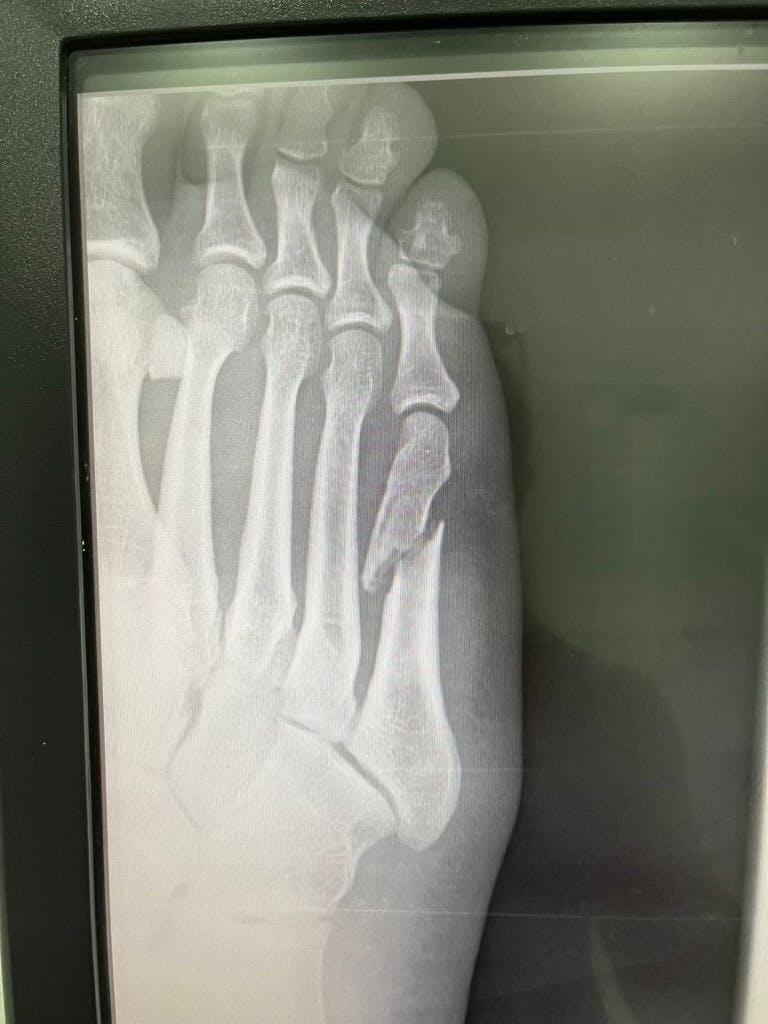

Det viser sig dog hurtigt, at det står meget værre til, og den efterfølgende dag må Jackie en tur til lægen for at få scannet foden:

– Her finder vi ud af, at ydersiden af foden er brækket midt over, så hele yderknoglen sidder forskudt, forklarer han.

I første omgang forsøger lægen af skubbe knoglen på plads. Men en efterfølgende scanning viser, at det slet ikke er lykkedes. Derfor må Jackie en tur på operationsbordet:

– Jeg er nødt til at komme på operationsbordet og i fuld narkose. De åbner op og opererer og sætter en metalstang ind igennem knoglen for at holde det sammen.